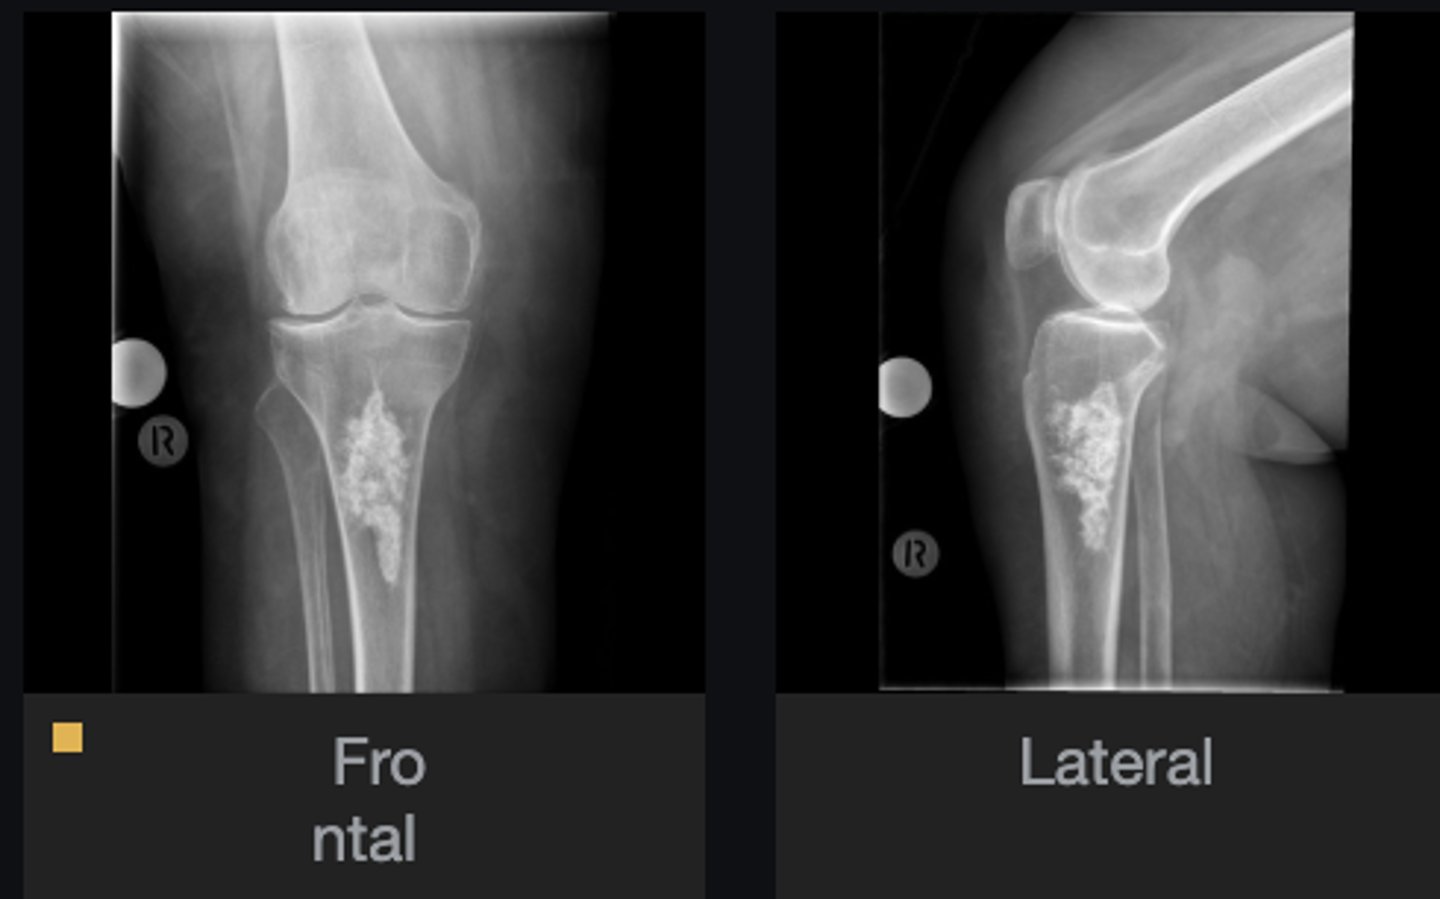

Lateral proximal tibia

Bone

<p>Bone</p>

- Longitudinal: epiphysis/metaphysis (up to joint surface)

- Eccentricity: eccentric

- Transverse: medullary

Location

- Lytic

- Geographic

- Short zone of transition

Behavior

<p>Behavior</p>

Cortex

<p>Cortex</p>

7

New cards

Nothing visible

Matrix

<p>Matrix</p>

8

None

Periosteal reaction

<p>Periosteal reaction</p>

9

Soft tissue swelling

Soft tissue involvement

<p>Soft tissue involvement</p>

10

Joint surface involved

Joint involvement

<p>Joint involvement</p>

11

Giant cell tumor

Most likely diagnosis?

<p>Most likely diagnosis?</p>

12

Refer to orthopedist or oncologist

Next step?

<p>Next step?</p>

13

Could be aggressive (20%)

Concerns/complications?

<p>Concerns/complications?</p>